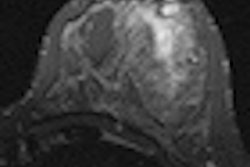

| MR images of invasive ductal carcinoma in a 62-year-old woman. Both images show how shifting MR spectroscopic imaging voxels can be performed retrospectively in all three spatial dimensions to allow improved matching with the pathologic area. Images courtesy of Radiology. |